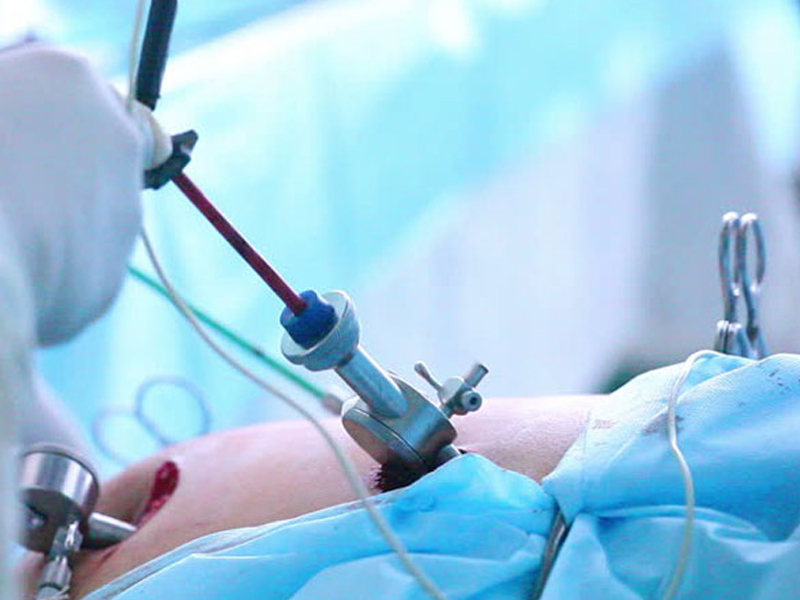

Laparoscopic Surgery

The process takes its name from the laparoscope, a slender tool that has a tiny video camera and light on the end. When a surgeon inserts it through a...